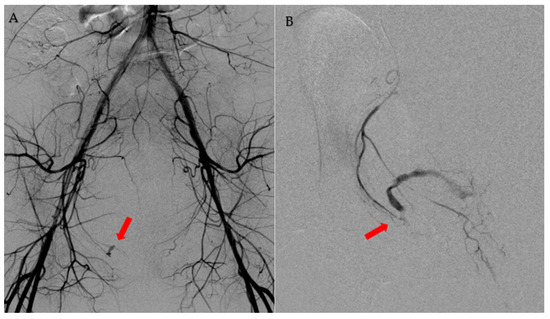

2. Case Presentation

| 6 | The present case | 40 | Nothing | Pain, hypotension, vaginal bleeding | Same day of OR | CT | Right pudendal artery | Gelfoam |